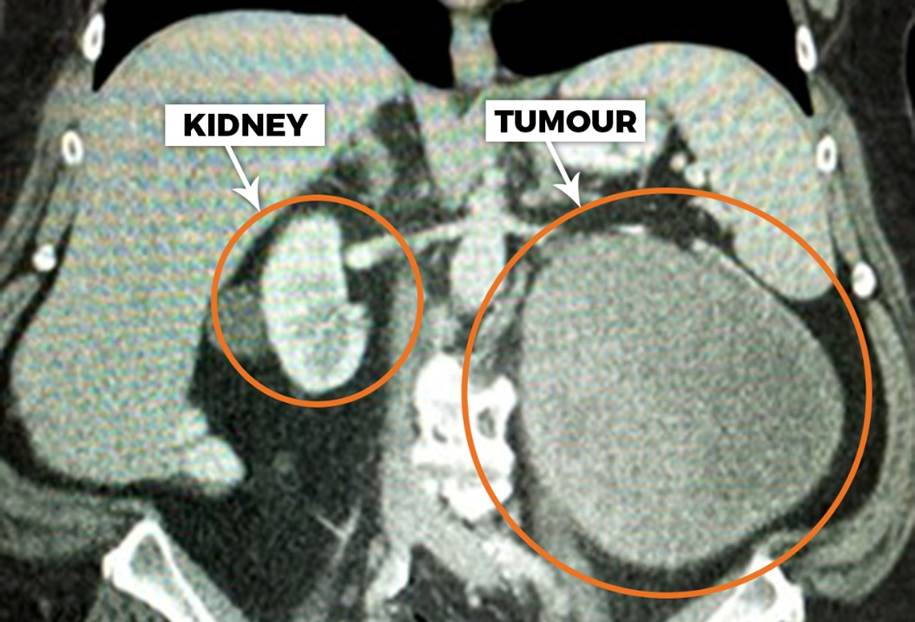

In urological surgery, treating kidney disease often involves choosing between two fundamentally different approaches.

The first approach is radical nephrectomy, where the entire kidney is removed along with the disease. This procedure is technically reliable and, in many cases, appropriate. When a kidney is severely damaged or affected by large or aggressive tumours, removal may be the safest option.

The second approach is kidney-preserving surgery, most commonly in the form of partial nephrectomy or reconstructive procedures. In these operations, the surgeon removes the diseased portion of the kidney while preserving as much healthy tissue as possible.